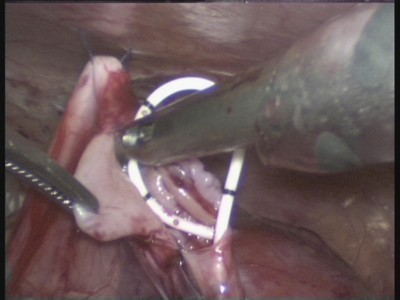

Az elmúlt 6 évben végzünk műtétet hydronephrosishoz laparoszkópos dostupa.Uspeshno üzemeltetett több mint 85 betegnél

Ábra. 11. A gyermek után 2 évvel a laparoszkópos műanyag LMS körülbelül gidronefroza.Imeetsya Tolka cső - biztonsági drenozh a hasüregben 3-5 napig.

Ábra. 12. A gyermek után 5 évvel laparoszkópos műtét.

12. ábra. A laparoszkópiás műtét.

Ábra. 13. Állítsa be a belső stent húgyvezetékében

14. ábra. Megjelenés képződik anastomosis húgyvezeték medence